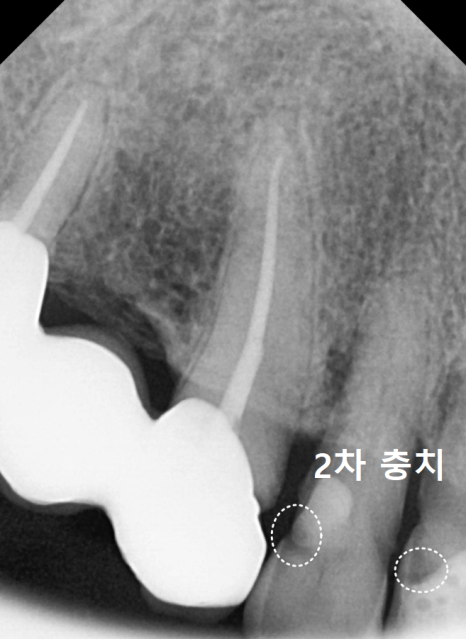

육안으로도 깊은 충치가 보였고,

과거에 레진으로 치료했던 부위 안쪽으로

2차 충치가 진행되고 있었죠.

방사선 사진을 살펴보니,

충치가 신경까지 아주 가깝게

진행되어 있었는데요...